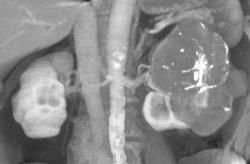

End Stage Kidney Disease (chronic Pyelonephritis)